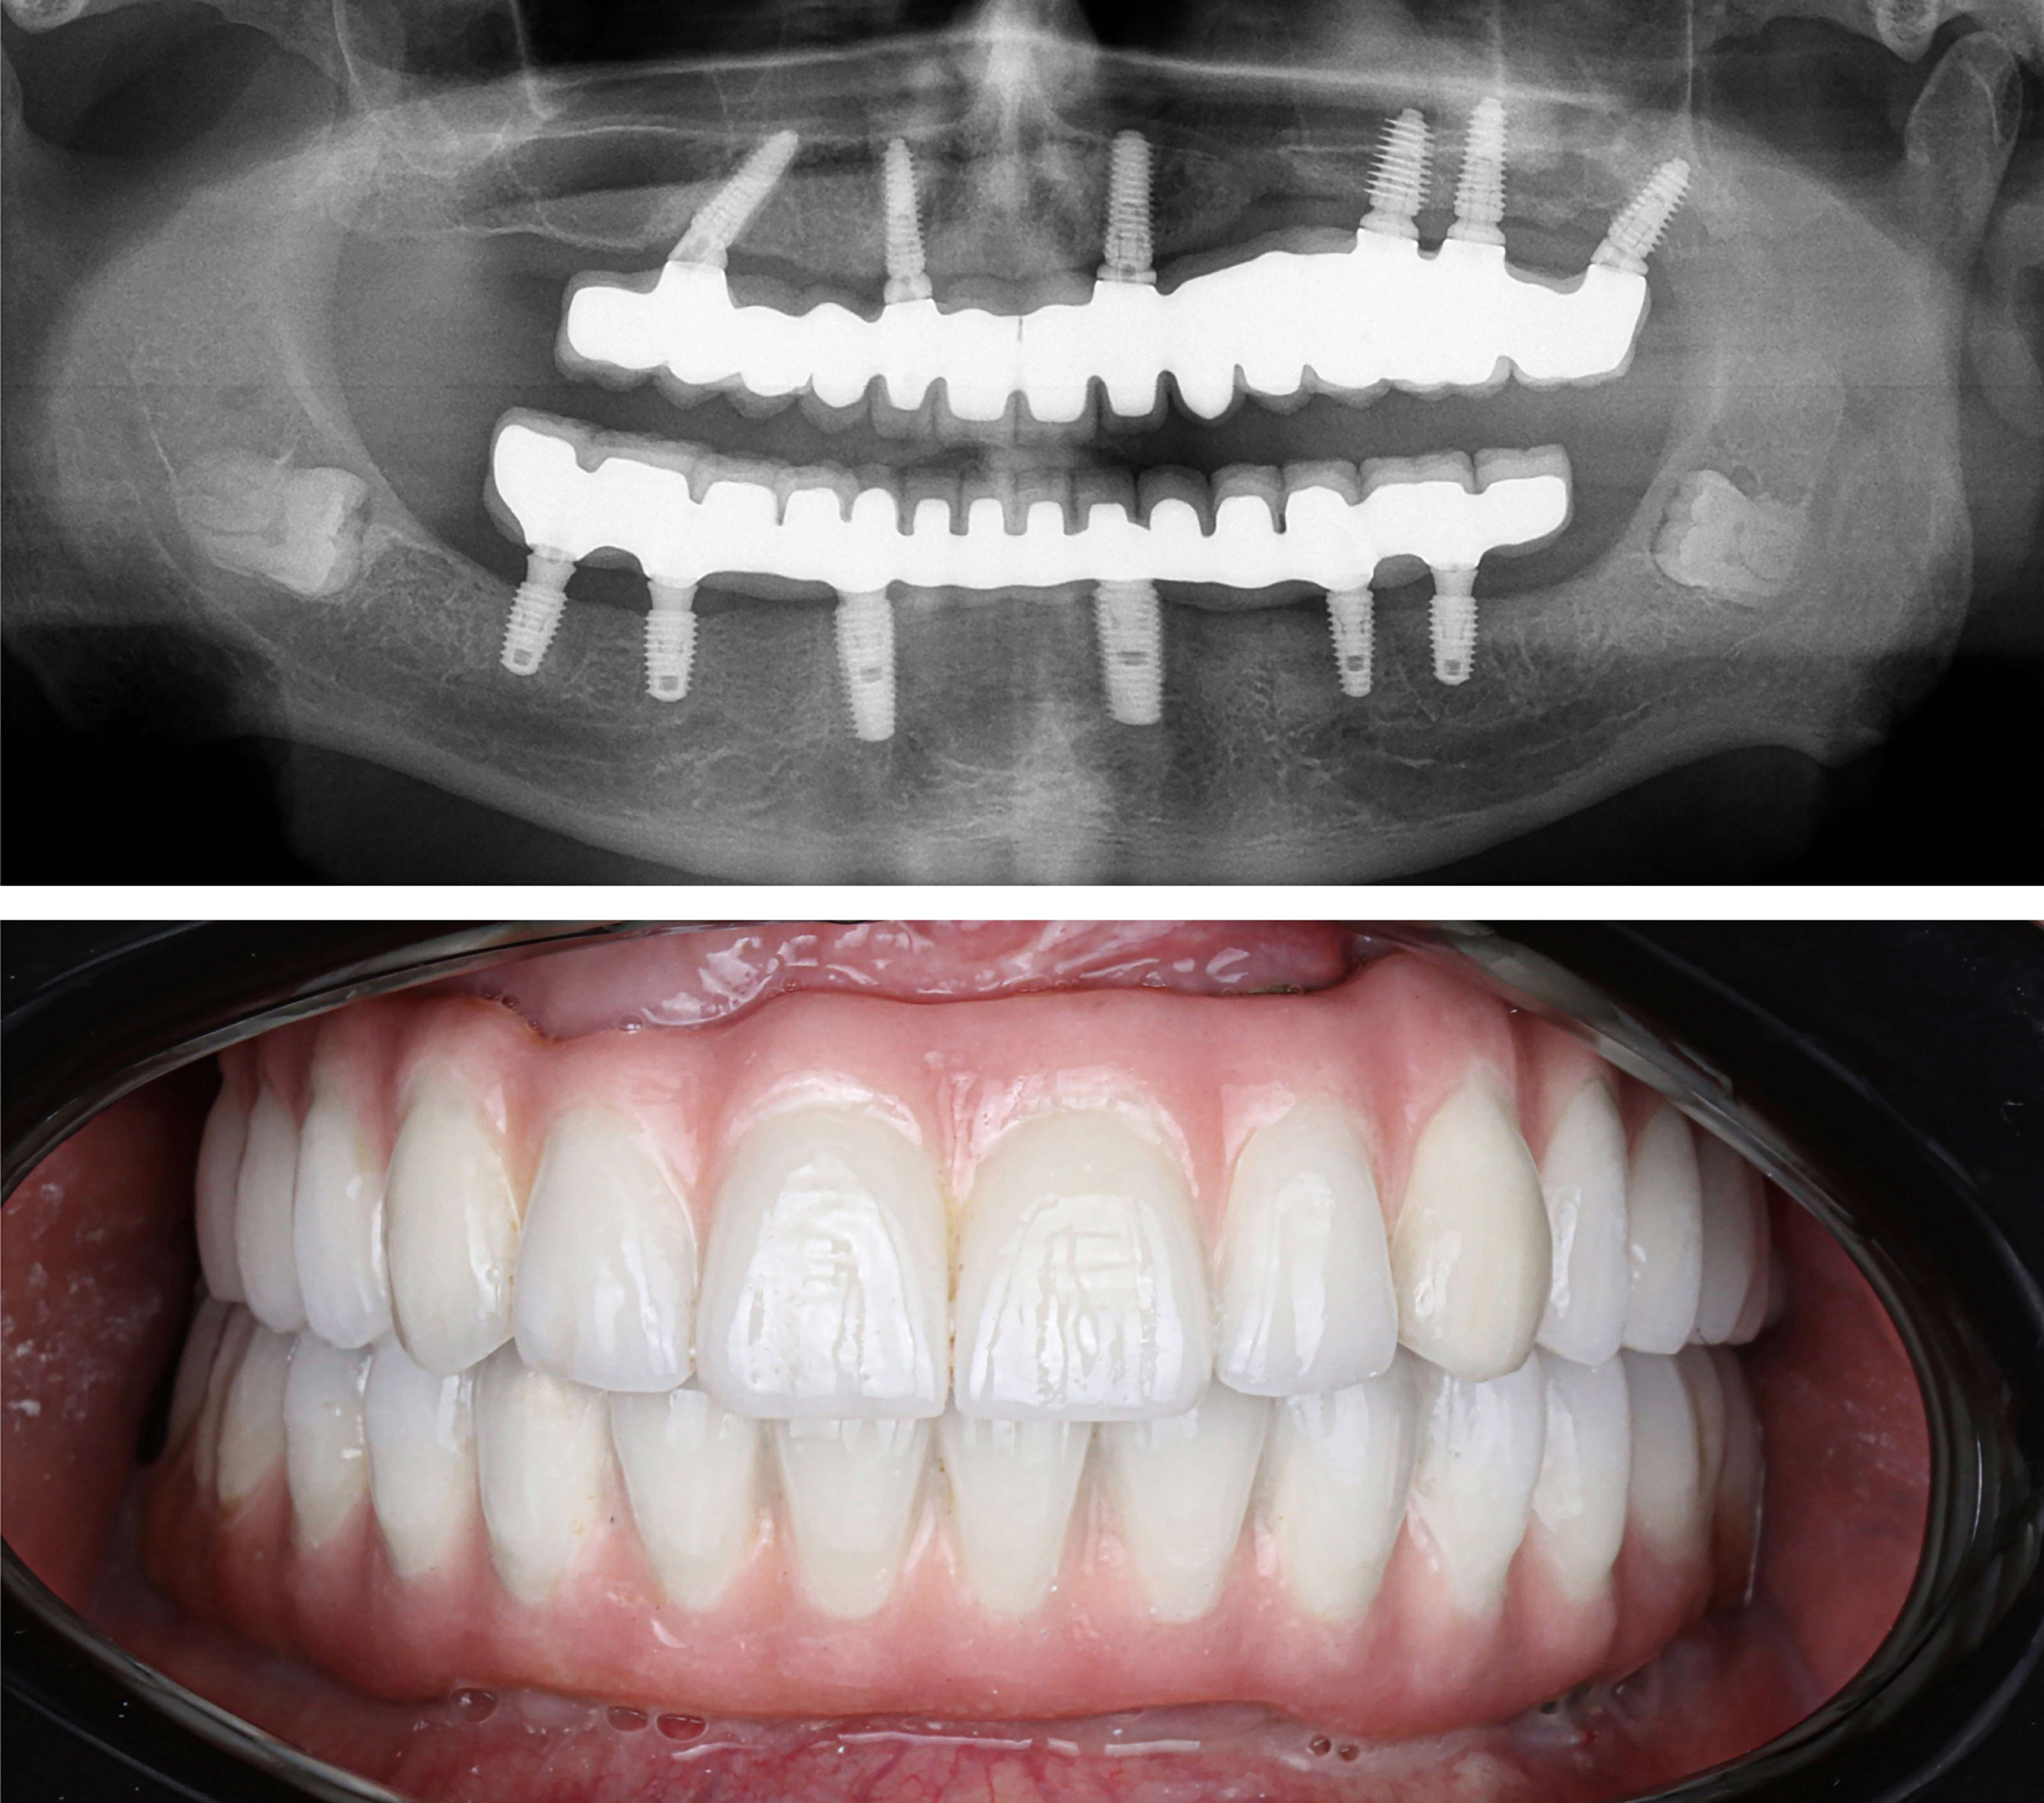

Example transformations achievable with dental implants

Includes Lifetime Warranty for FREE. Protects your investment.

Includes surgical placement of 6 implants.

Includes abutments

Includes healing teeth.

Includes final ultra aesthetic zirconia teeth.